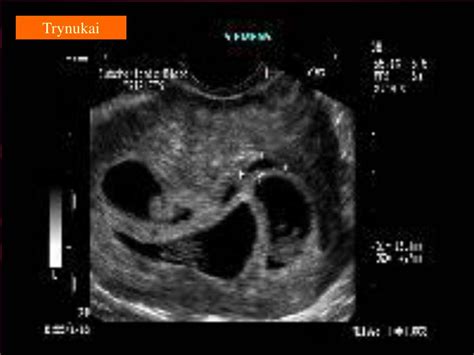

Kraujavimas nėštumo pradžioje, nepatikslintas, dažniausiai susijęs su reprodukcine sistema, ypač su moters gimda ir kiaušidėmis. Nėštumo metu gimdoje vyksta daug pokyčių, kad būtų užtikrintas embriono vystymasis. Gimdos gleivinė (endometriumas) storėja, kad galėtų priimti apvaisintą kiaušinėlį. Kraujavimas nėštumo pradžioje, nepatikslintas, yra simptomas, kuris gali pasireikšti įvairiais nėštumo etapais, bet dažniausiai pasireiškia pirmaisiais trimestrais. Ši liga yra svarbi, nes ji gali rodyti tiek normalius fiziologinius procesus, tiek rimtas problemas, tokias kaip persileidimas ar užsikimšimas. Kraujavimo nėštumo pradžioje priežastys gali būti įvairios. Kraujavimas nėštumo pradžioje diagnozuojamas naudojant kelis metodus. Gydytojai gali atlikti kraujo tyrimus, kad įvertintų hCG (human chorionic gonadotropin) hormonų lygį, ultragarso tyrimus, kad patikrintų embriono būklę ir gimdos struktūrą. Kraujavimo gydymo galimybės priklauso nuo priežasties. Jei kraujavimas yra lengvas ir nesusijęs su rimtomis problemomis, gydytojai gali rekomenduoti poilsį ir stebėjimą. Esant sunkiam kraujavimui ar persileidimo grėsmei, gali prireikti hospitalizacijos ir medicininio gydymo. Naujoviškos terapijos galimybės, tokios kaip hormonų terapija, gali būti taikomos, siekiant stabilizuoti nėštumą. Svarbu, kad moterys, patiriančios kraujavimą, gautų tinkamą medicininę priežiūrą ir konsultacijas, kad būtų užtikrinta jų ir vaisiaus sveikata.

Diagnozuojant kraujavimą nėštumo pradžioje, gydytojai gali atlikti: